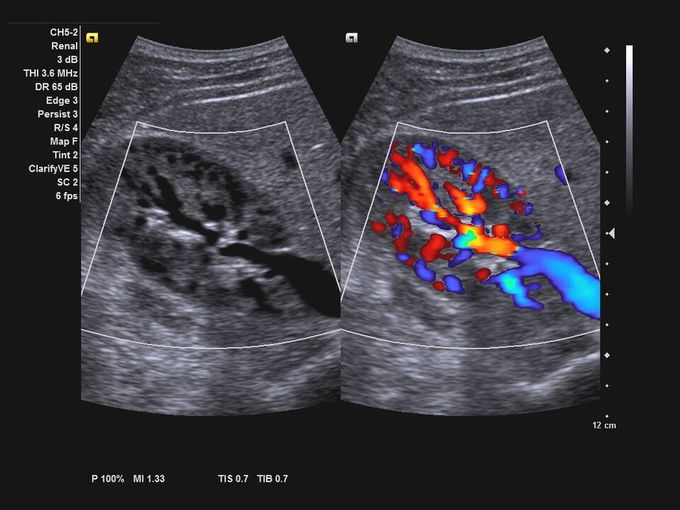

Кроме новой техники, можно заказать восстановленные медицинские системы: ультразвуковые сканеры, томографы, флюороскопы, ангиографы и хирургические установки С-дуга.